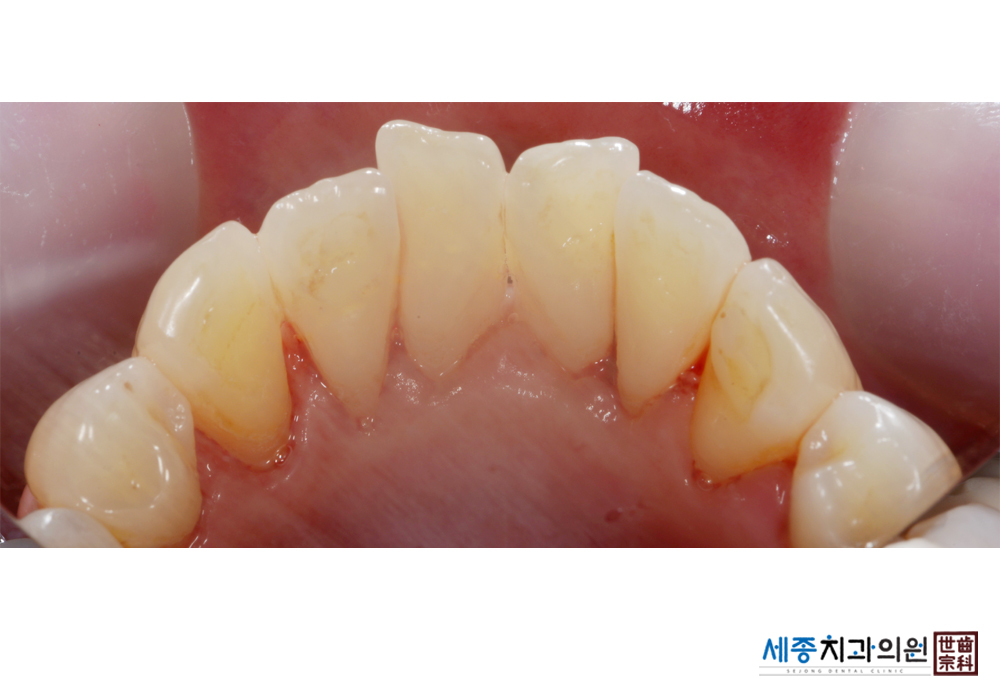

[스케일링] 치주질환 예방 스케일링 치료

치료전 : 2019-01-07

치료후 : 2019-01-07

가글마취&저주파 스켈러를 사용한 스케일링